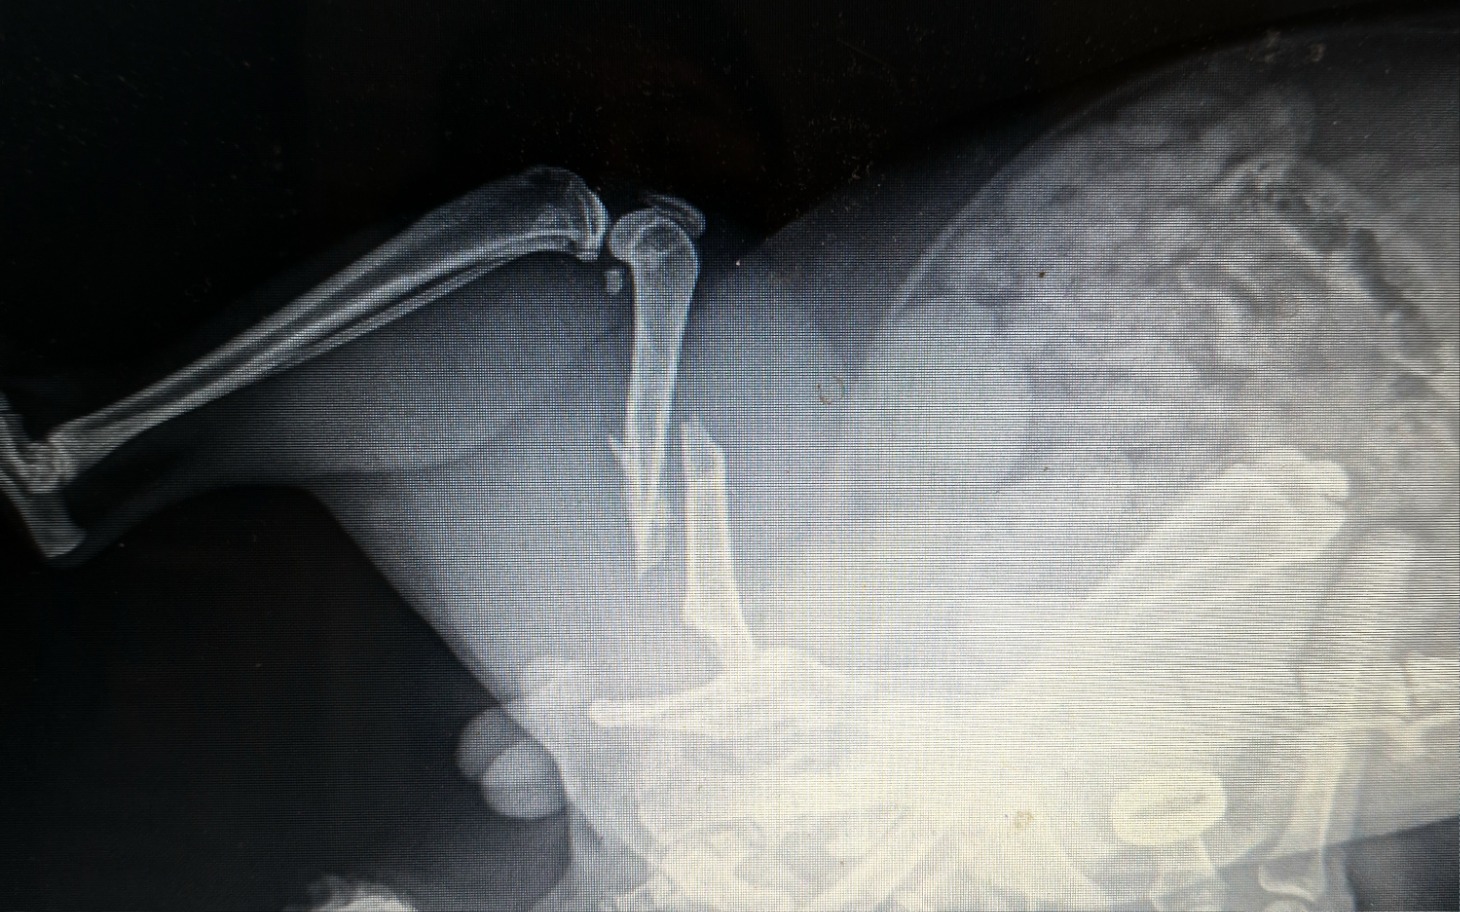

Zbieramy na tej zbiórce na leczenie i sterylizacje oraz operację ortopedyczną dla kota spod bloków Miśka

Po operacji i rekonwalescencji oraz kastracj ma szansę na adopcje, bo to jest nasz główny cel.